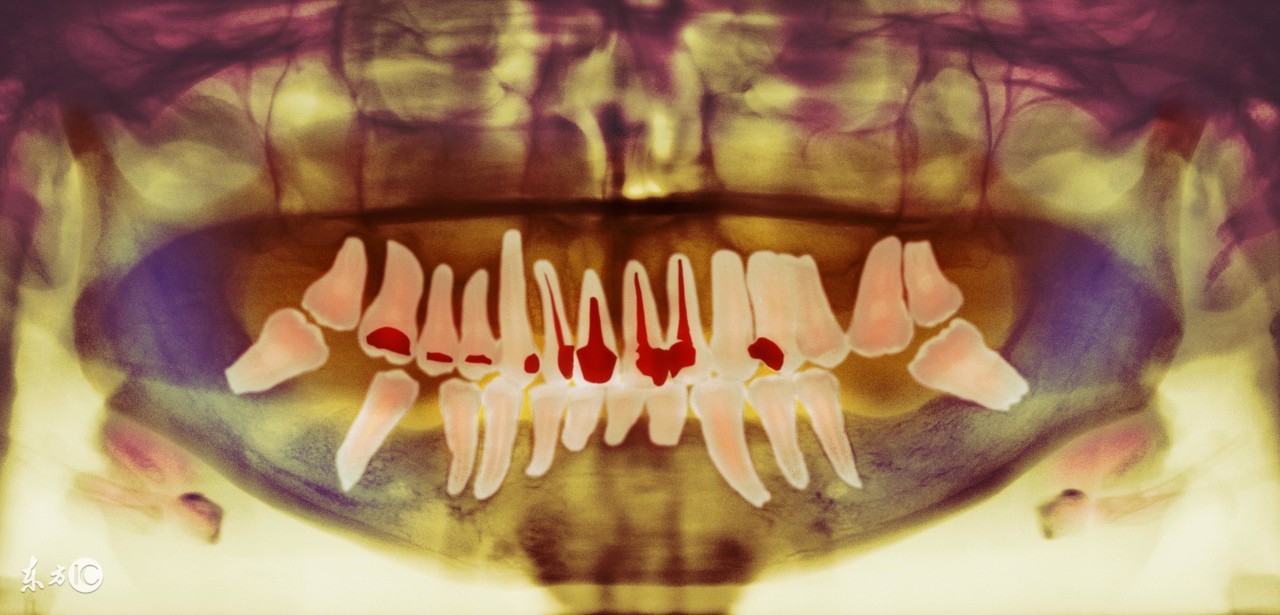

简单的说,有牙髓炎(蛀牙已经伤及牙髓),根尖周炎,引起这些的有蛀牙,外伤,缺损,隐裂,一旦牙齿有剧烈疼痛,特别是下午晚上,那就要到医生那里检查你的蛀牙或者伤牙是否已经感染了牙髓炎。

牙齿根管治疗后,因为原本蛀牙严重,牙体缺损严重,或因根管治疗将牙髓腔打开便于清除,因而丧失一些牙体。而且根管治疗后,牙齿没有了牙髓,失去了牙髓腔中神经,血管,淋巴等营养供应,使得牙齿本身变得比较脆弱易断裂。